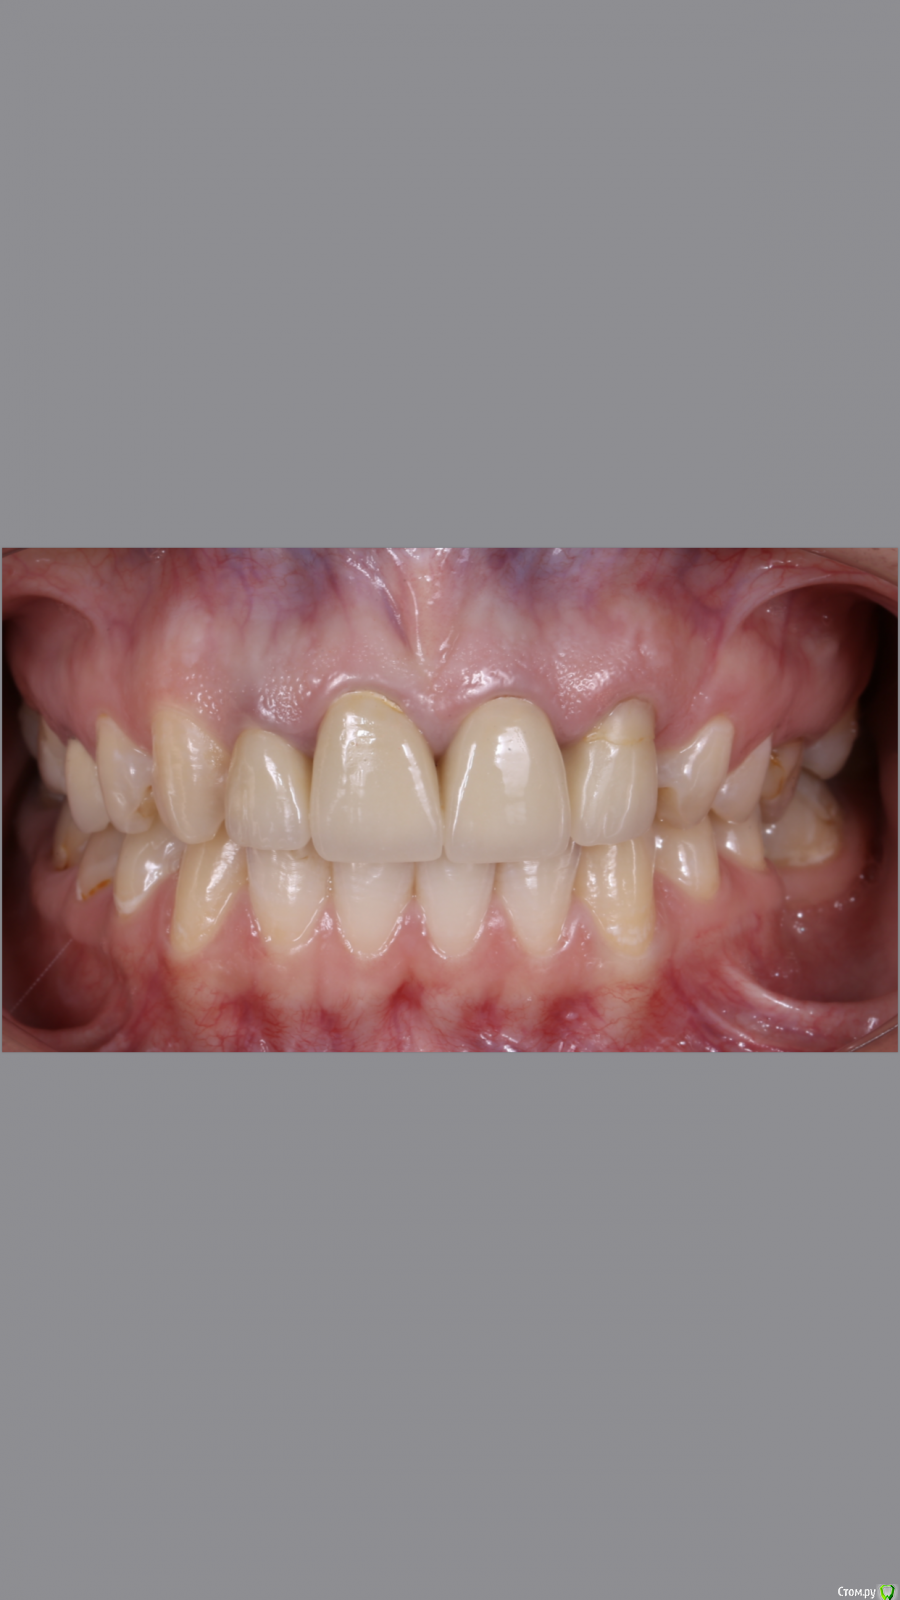

dr.Dre Опубликовано 8 июня, 2019 Поделиться Опубликовано 8 июня, 2019 Добрый вечер.Коллеги помогите грамотно скласть план лечения?С чего начинать ,терапия,ортодонтия ортопедия Ссылка на комментарий

johniola Опубликовано 8 июня, 2019 Поделиться Опубликовано 8 июня, 2019 Реэндо+орто+протезирование 1 Ссылка на комментарий

Monkey Опубликовано 19 июня, 2019 Поделиться Опубликовано 19 июня, 2019 Добрый вечер.Коллеги помогите грамотно скласть план лечения?С чего начинать ,терапия,ортодонтия ортопедияСанация, удаление 8-х, ортодонтическое лечение с раскрытием места 36,23 (заодно и среднюю линию откорректируете), протезирование Ссылка на комментарий